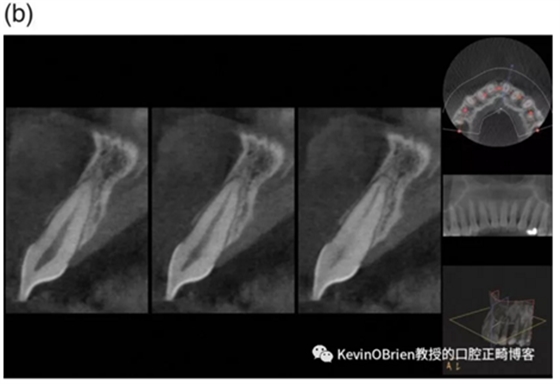

我們都熟悉正畸誘導(dǎo)性牙根吸收(Orthodontically Induced Root Resorption, OIRR)。一些研究把牙根吸收量與幾個(gè)可能原因聯(lián)系了起來,例如治療持續(xù)時(shí)間,矯治器類型以及施加的力。雖然這些研究給我們提供了有用的信息,但其大多數(shù)都采用了2D的頭顱側(cè)位X線片。CBCT影像的出現(xiàn)使得對OIRR的更精確測量成為可能。因此,作者們做了一項(xiàng)新的研究去探究這個(gè)問題:

“用CBCT成像測量的OIRR的平均值是多少?”